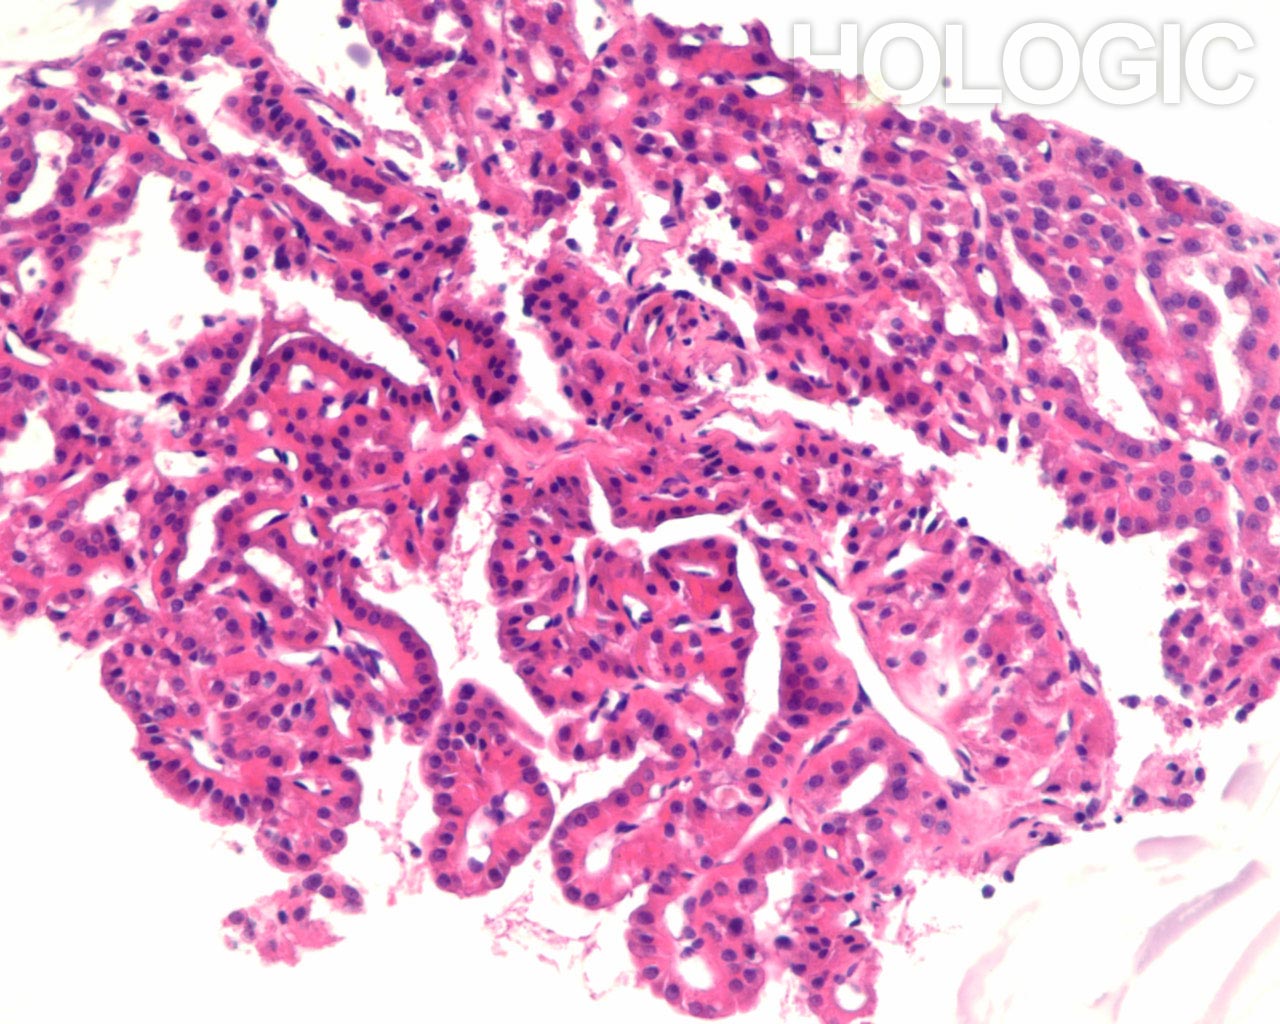

Met celblokken kan de afmeting van de follikel beoordeeld worden op een manier die een aanvulling vormt op de ThinPrep-glaasjes. Om een follikel als groot aan te merken, moeten de folliculaire cellen over een tamelijke grote afstand 2-dimensionaal georganiseerd zijn; als de follikels klein zijn, bevinden de cellen zich niet in een brede 2-dimensionale, platte laag. Het is verrassend moeilijk het eens te worden over de definitie van ‘macrofolliculair’ [9]. Acht tot 10 folliculaire celdiameters lijkt een redelijke definitie voor de macrofolliculaire colloïd fragmenten [9], of voor de diameter van platte, 2-dimensionele macrofolliculaire lagen. In weefselcoupes die loodrecht op een macrofolliculaire groep zijn gesneden, zien de macrofollikels eruit als een lineaire ordening van ten minste 8 folliculaire cellen. Als de sectie in het vlak van een macrofolliculaire groep snijdt, kan men gemakkelijk een solide uitziende celmassa tegenkomen die analoog is aan een weefselcoupe die tangentieel recht door de ductale cellaag snijdt in een schildklier biopsie. Net als pathologen een dergelijke tangentiële coupe kunnen herkennen en kunnen onderscheiden van ductale hyperplasie, kan men een tangentiële coupe door macrofolliculaire groepen herkennen. Dit wordt hieronder geïllustreerd. Microfollikels hebben per definitie een hoge ratio tussen de cellen en het colloïd en de cellen kunnen niet in een brede 2-dimensionele laag liggen. In celblokcoupes vertonen microfollikels geen lange lineaire organisatie van cellen. Renshaw et al. vonden een significante grijze zone onder experts in het onderscheid tussen microfolliculaire en macrofolliculaire groeperingen op cytologische preparaten [9].Een van de belangrijkste grijze gebieden betreft het probleem van folliculaire cellen die artefactueel op elkaar zijn gestapeld. Deze artefactuele stapeling van cellen lijkt gemakkelijker te diagnosticeren in weefselcoupes. Een ander probleemgebied betreft die gevallen waarin microfollikels en macrofollikels door elkaar zijn gemengd. Het is ons en anderen opgevallen dat benigne stromanodulen vaak plat cytoplasma vertonen in de cellen van de microfollikels. De robuustere cellen van een folliculair neoplasma tonen vaak veelal kubusvormige of zelfs cilindrische, folliculaire cellen die de microfollikels bekleden [7]. Deze kenmerken zijn duidelijk in celblokcoupes en worden hieronder geïllustreerd.

Benigne folliculaire nodulen vertonen vaak een bijmenging van cytologisch verschillende typen folliculaire cellen. De follikels van folliculaire neoplasmen zijn meestal uniform van aard. Hoewel het uiterlijk van de follikels in een cytologisch preparaat van groep tot groep kan worden vergeleken, kan deze benadering van het beoordelen van de klonaliteit soms moeilijk zijn. Het kan bijvoorbeeld onmogelijk zijn om te weten of de FNA-naald buiten het neoplasma monsters heeft genomen. Met celblokken kunnen de morfologische kenmerken van waarlijk aangrenzende follikels over een bereik van enkele honderden microns geëvalueerd worden, zoals hieronder geïllustreerd wordt.